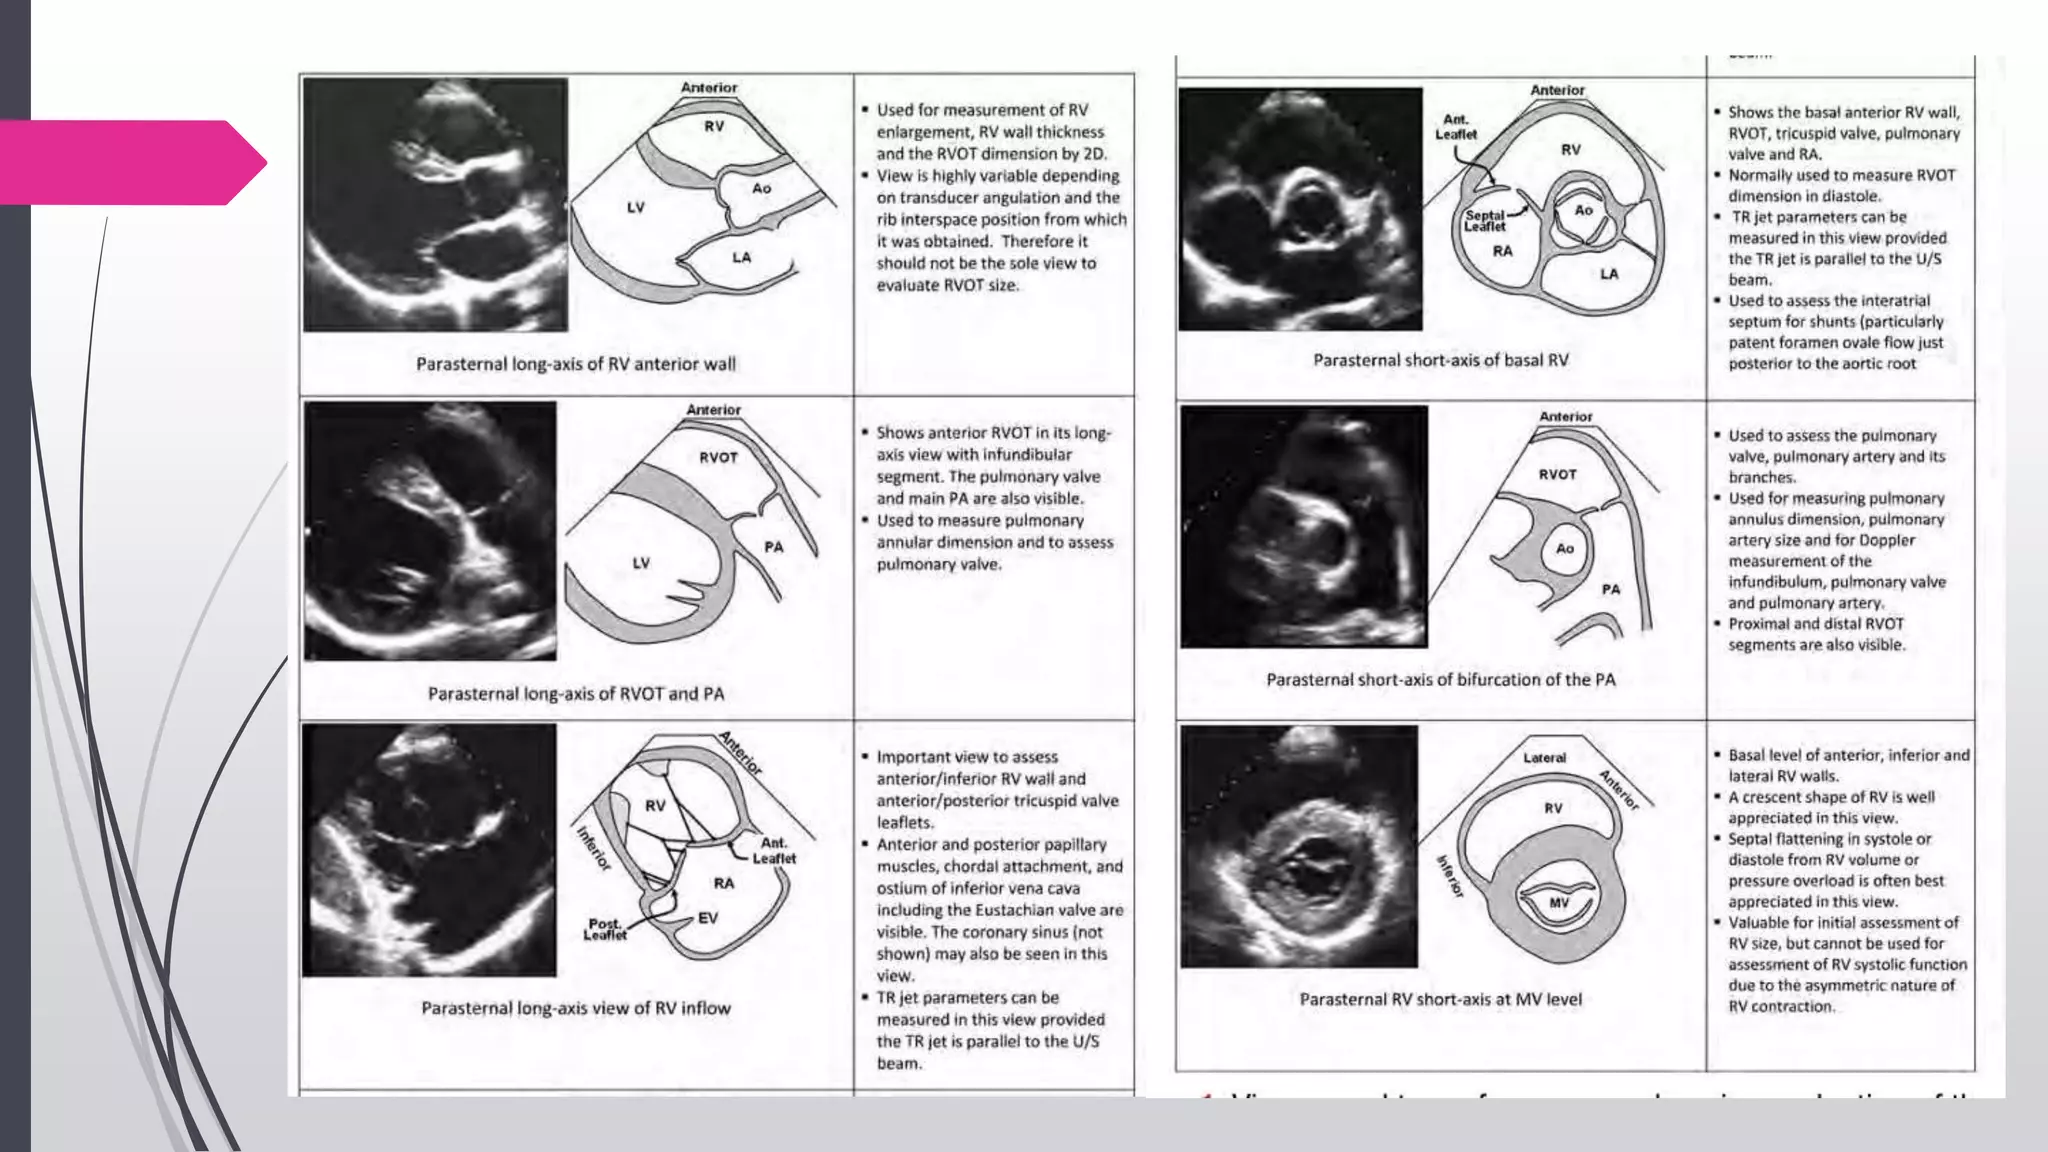

Key views

PLAX & RV inflow

Initial screening of

RA/RV, TR jet

PASX

IVS flattening, TR jet,

RVOT outflow pattern,

PR jet

A4C & modified A4C

RA/RV size, TV, annular

motion, TR jet, IAS

Subcostal

RVH, IVC

2D and M-mode: RVOT Size

 Best viewed from the left parasternal and subcostal windows

 Size of the RVOT measured at end-diastole on the QRS deflection.

 In PLAX view, a portion of the proximal RVOT can be measured

(RVOT-Prox)

 In PSAX, RVOT linear dimension measured from

Anterior aortic wall to the RV free wall above the aortic valve (RVOT-Prox)

&

Just proximal to the pulmonary valve (RVOT-Distal)

 PLAX view of RVOT - used in evaluation for ARVD